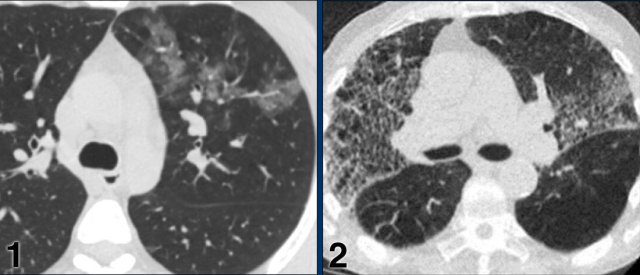

CORADS 4

In CO-RADS 4 the level of suspicion is high.

Mostly these are suspicious CT findings but not extremely typical:

• Unilateral ground glass

• Multifocal consolidations without any other typical finding

• Findings suspicious of COVID-19 in underlying pulmonary disease.

Case 1

7 days of compaints

CT: unilateral areas of GGO in left upper lobe.

PCR: positive.

Case 2

CT: bilateral GGO in a patient with emphysema.